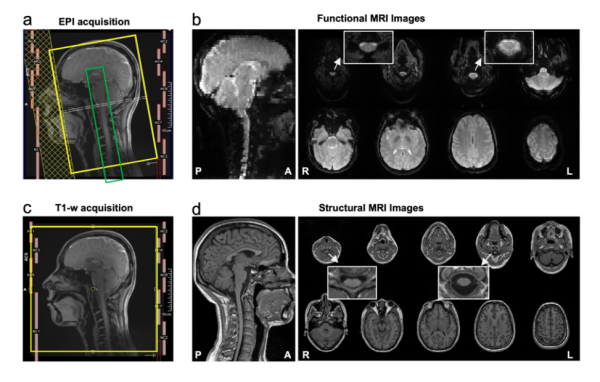

CoSpine成像方案實(shí)現(xiàn)了覆蓋大腦、腦干、小腦及頸段脊髓的單視野同步采集。這一方案融合多頻帶并行采集與并行重建算法,可保持1.5毫米高空間分辨率,提升了時(shí)間采樣效率與圖像質(zhì)量。該策略使皮層-腦干-脊髓神經(jīng)信號(hào)得以在一次掃描中連續(xù)獲取,為腦–脊髓功能交互研究奠定了方法學(xué)基礎(chǔ)。

CoSpine功能與結(jié)構(gòu)成像的采集方案及示意圖